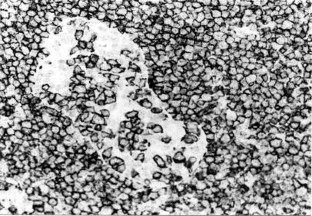

Fig. 2